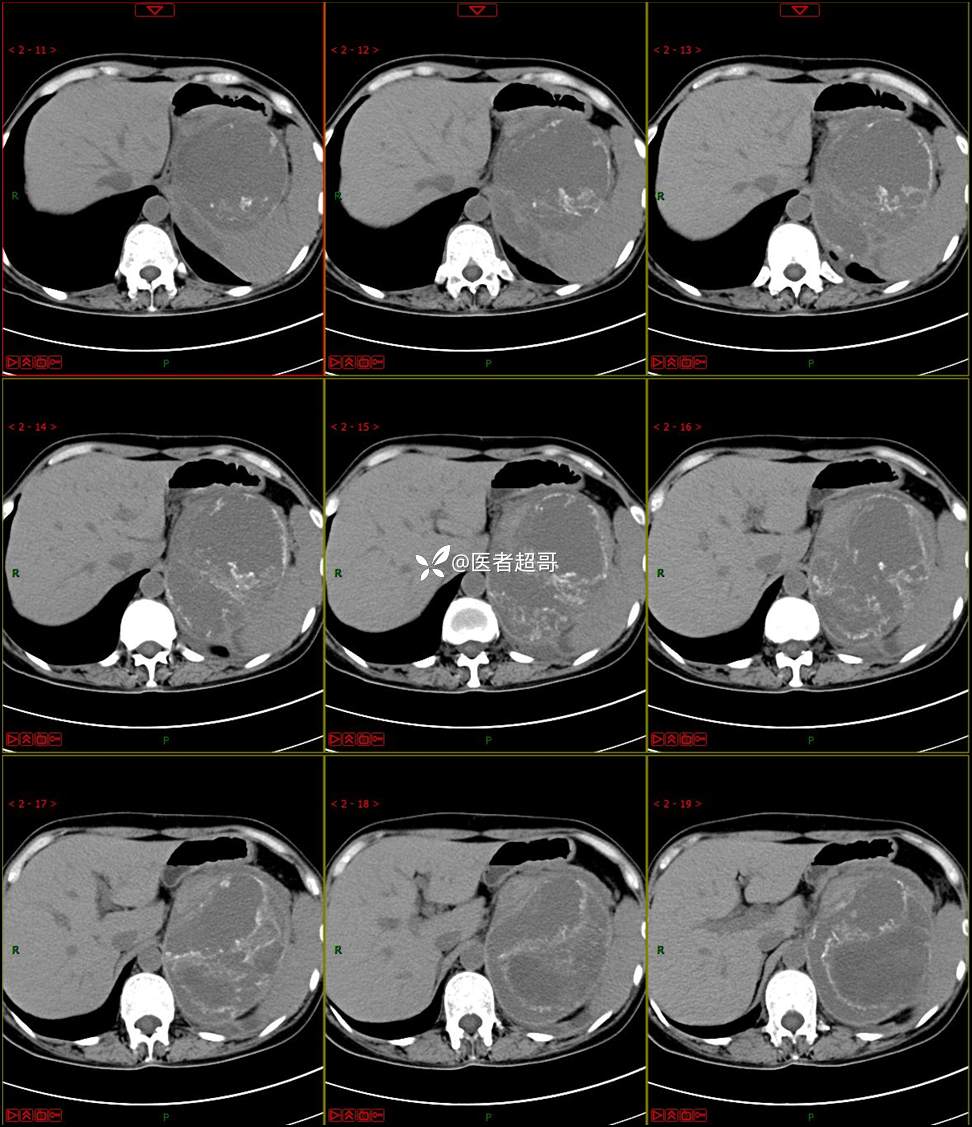

【影诊笔记768】肾脏肿瘤?肾上腺肿瘤?请诊断分析!

女 57岁 0200908 01

主 诉:发现左肾肿物7月余

现病史:患者7月前因左侧腹部疼痛不适,就诊市人民医院,行CT平扫:左侧肾上腺区混杂密度肿块,考虑肿瘤合并出血,行保守治疗后症状缓解出院,左侧下腹部及左侧髋部疼痛不适,无尿频、尿急、尿痛,无肉眼血尿,无寒战、发热,今患者为求进一步诊治,就诊我院,门诊以“左肾肿物”为诊断收入院,患者自发病以来,神志清,精神可,饮食睡眠可,小便如上述,大便正常,体重未见明显改变。